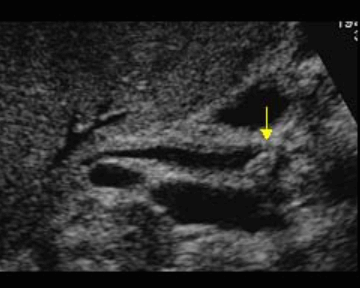

US finding

- 담낭관 또는 담낭 경부에 결석이 확인된다.

- 총간관(CHD) 또는 담낭관(cystic duct)의 확장소견이 보인다.

- 간내외 담관의 확장이 관찰된다.